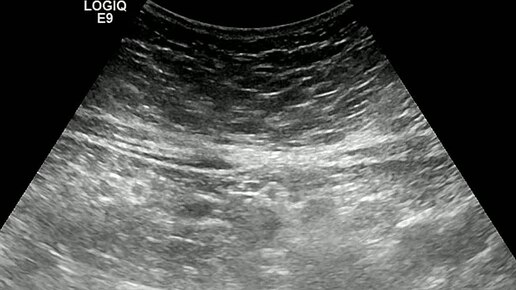

Видео к статье: "Свободная жидкость в брюшной полости"https://dzen.ru/a/Z-1KdOK-KyrjRiGF

Ультразвуковые находки от врача УЗД Зорина Я.П.